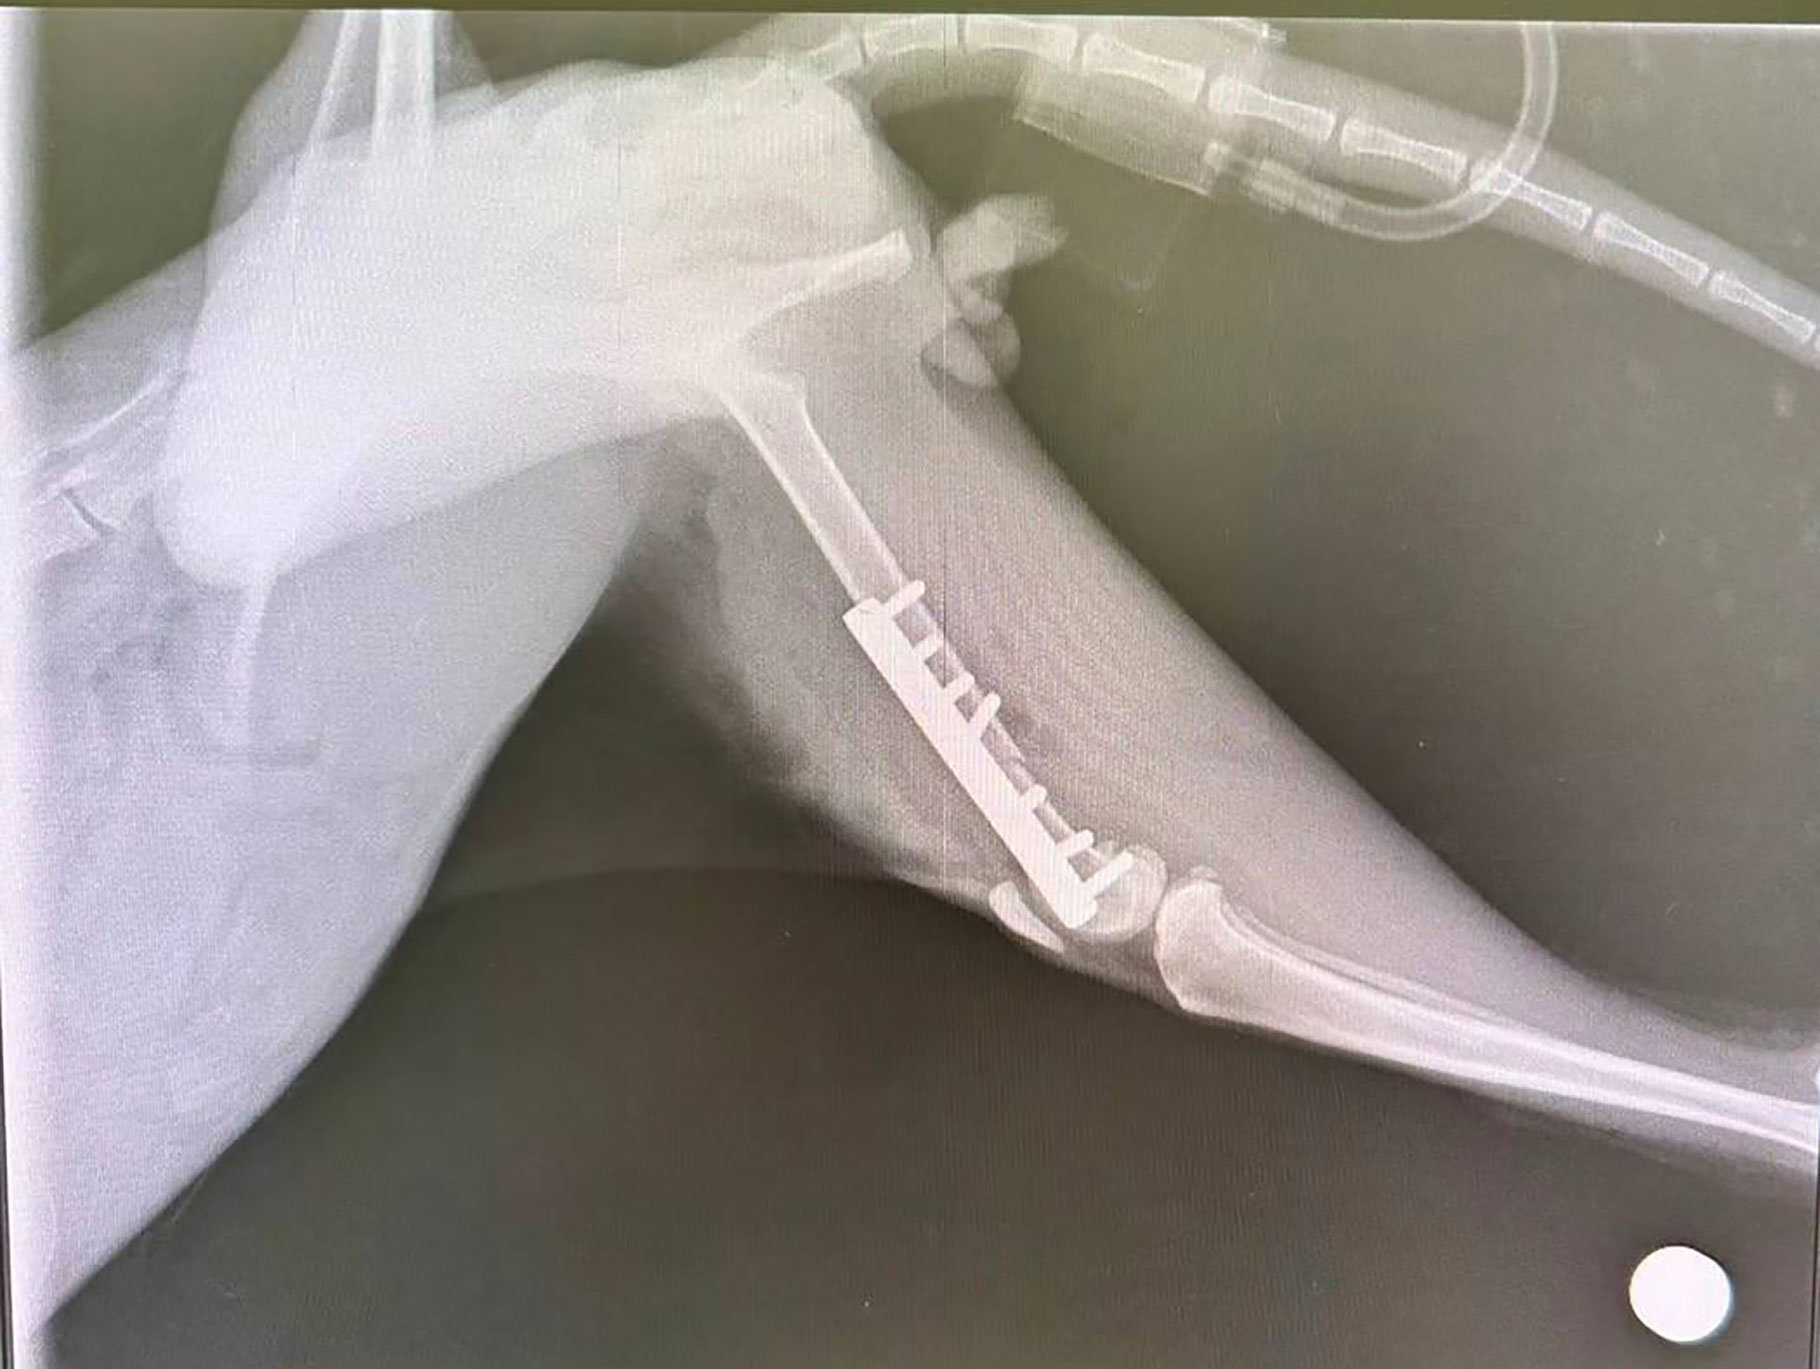

手術後のレントゲン写真です

骨折していた脚はきれいに繋がっています